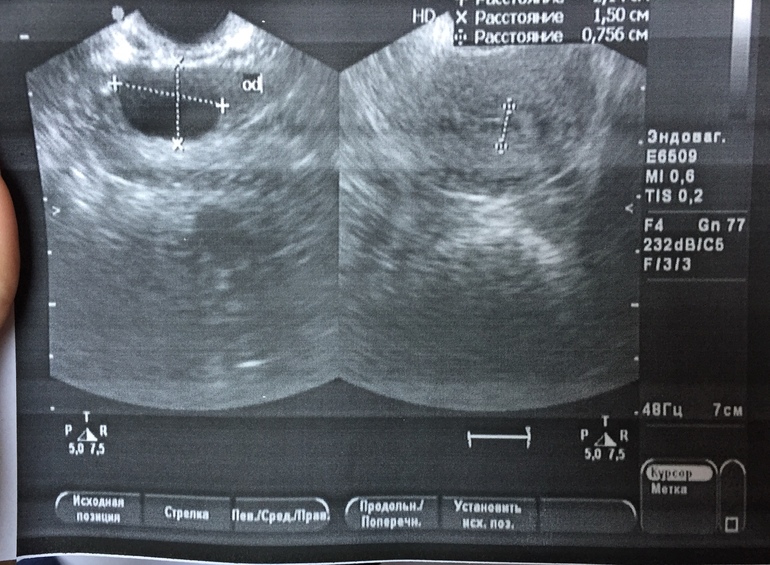

Девчонки,подскажите,что это может быть.Узистка так и не сказала внятно,склоняется к аднекситу в левой трубе.А может это просто фолликул?иоможет кто то сталкивался с таким.

«Рядом с левым яичником виз-ся образование,с утолщенным контуром,просвет жидкостный.ф 19*14мм.а может это внематочная,уже думаю о самом страшном((фото узи

Фух.надеюсь...и тоже странное заключение

Слева-ПОХОЖЕ,визиализируется орнамент трубы,не исключено хронический аднексит....

Она написала возле яичника.и сказала,немного труба расширена,но почему то не написала об этом..вообщем все странно это

Тоже сразу подумала о том, что врач видит расширенную трубу. ХГЧ не назначили , возможно, так как фаза цикла совершенно не подходит. Но я бы и аднексит не ставила. Либо сальпингит, либо гидросапинкс.